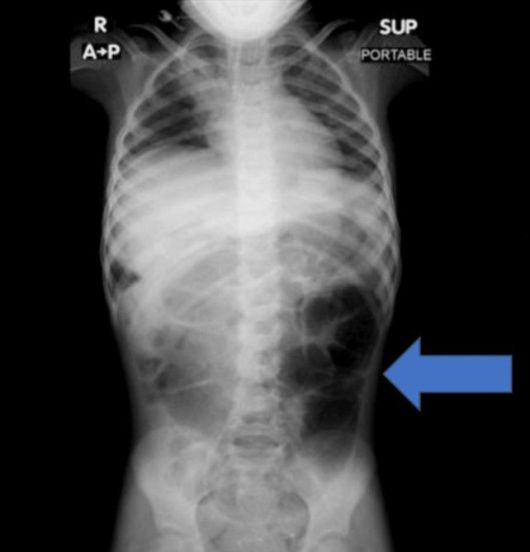

20일 의학 저널 '큐레우스(Cureus)' 실린 보고에 따르면, 사우디아라비아에 거주하는 6세 여자아이는 수주간 이어진 복통과 소화 장애 증상으로 병원을 찾았다. 정밀 검사를 진행한 결과, 의료진은 위 내부에 비정상적으로 큰 이물질이 자리 잡 것을 확인했다.

수술을 통해 제거된 물질의 정체는 다량의 머리카락이 엉켜 형성된 덩어리였다. 해당 덩어리는 위에 머무는 데 그치지 않고 소장 일부까지 길게 이어진 상태였던 것으로 전해졌다.

의료진은 보고서를 통해 "소아 환자에게 반복적인 복통이나 구토, 식욕 저하 증상이 장기간 지속될 경우 위장관 내 이물질 가능성을 염두에 둬야 한다"며 "영상 검사를 통한 조기 진단과 신속한 치료가 중요하다"고 강조했다.

라푼젤 증후군은 머리카락을 반복적으로 뽑는 행동과 이를 삼키는 습관이 함께 나타나면서, 섭취된 모발이 위장 안에 쌓여 덩어리를 이루는 매우 드문 질환이다.